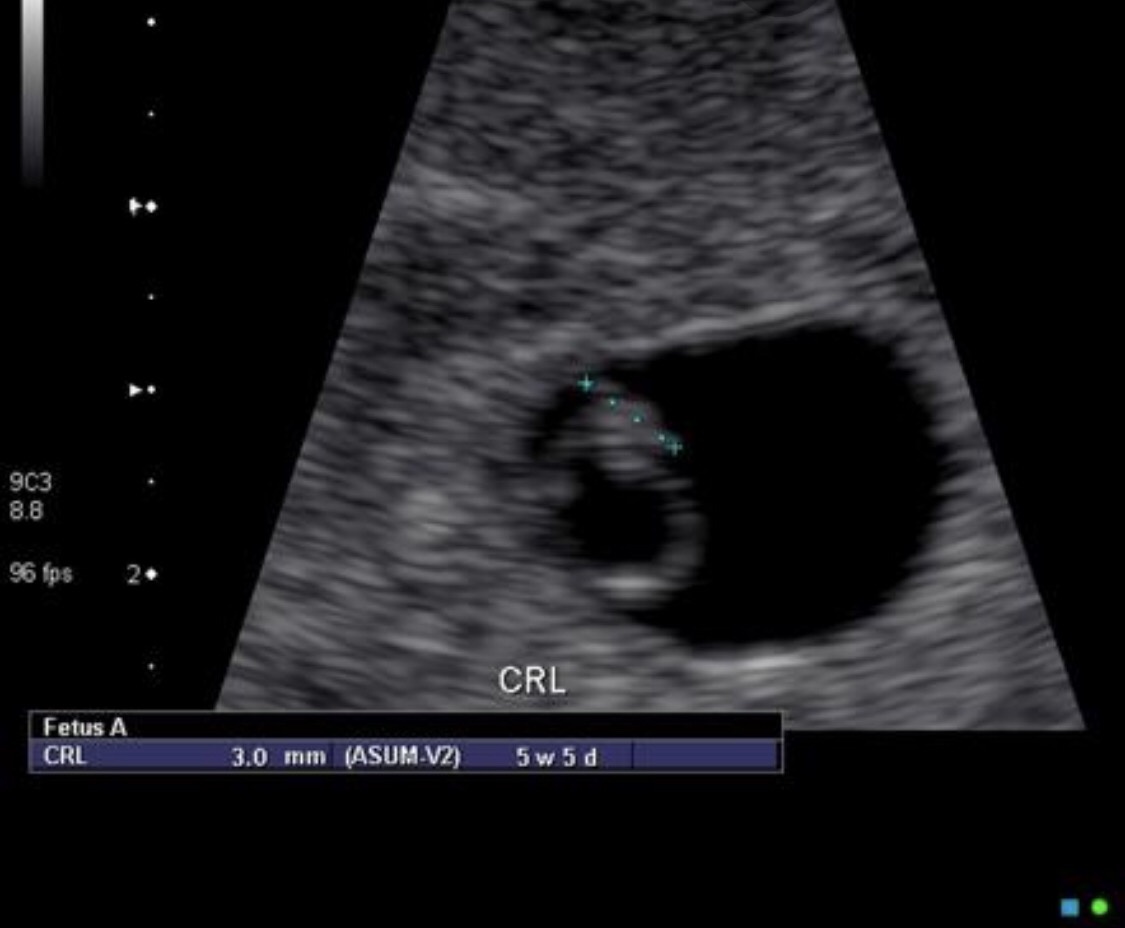

Can You See Anything On An Ultrasound At 4 Weeks. I am afraid i lost the baby but have also read that it could be too early. Usually its a microscopic ball of cells at that point. In early pregnancy, a transvaginal ultrasound is much more accurate than an abdominal ultrasound. Trust me i know its hard, but stress is not good for you or the baby. The gestational sac is that black area, while the yolk sac is the small white circle you see at the sac’s upper left. Between 5 ½ to 6 ½ weeks, a fetal pole or even a fetal heartbeat may be detected by vaginal ultrasound. Hope everything turns out ok. Has anyone ever had the doctor find nothing in her uterus at 4.5 weeks? Sent from my iphone using netmums 0 like similar threads early pregnancy signs and symptoms scan at 4 weeks, pregnancy in unknown location This will be my 3rd pregnancy and i dont know what to think of it. “today, twins can usually be diagnosed as early as six to seven weeks of the pregnancy,” he adds. What it would look like. When identified on the ultrasound, the diameter of the sac is around 2 to 3 millimeters and is seen as a white rim around a clear center in your uterus.

The heartbeat of the fetus can be seen during an ultrasound. 4 weeks pregnant but no sign of baby on ultrasound. I had an early scan at around 4.5 weeks and they couldn't see anything so they did an internal scan and also couldn't see anything apart from my womb lining thickening, which they said was a good sign. If a transvaginal ultrasound is used, the sac may be visible a week or two earlier—at about 5 weeks. It is not possible to determine fetal size at this stage. “you can guess as much as you want, but until you have the ultrasound examination, it’s all just speculation,” says dr. Has anyone ever had the doctor find nothing in her uterus at 4.5 weeks? At this time the average diameter of the sac is 2 to 3 millimeters. 4 weeks pregnant ultrasound the amniotic sac and fluid are forming into protective cushioning for baby. Nothing seen in ultrasound at 4,5 weeks, can it be miscarriage or ectopic.

The Gestational Sac Is Usually Seen On Ultrasound By 5 Weeks Gestational Age But Is Sometimes Seen As Early As 4 Weeks Gestational Age.

The gestational sac increases in diameter by 1.13 mm per day and initially measures 2. Around 6 or 7weeks, an abdominal ultrasound will show the gestational sac. If the cramps are like period pains then they are normal in pregnancy.

The fetal pole is the first visible sign of a developing embryo. It is not possible to measure fetal size at this stage. When identified on the ultrasound, the diameter of the sac is around 2 to 3 millimeters and is seen as a white rim around a clear center in your uterus.